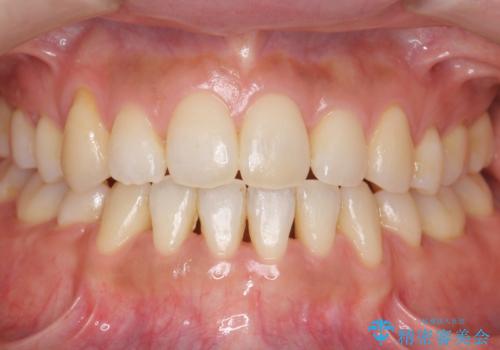

八重歯 上下の正中のずれ 40代で抜歯矯正

時間はかかりましたがしっかり治療することができました。